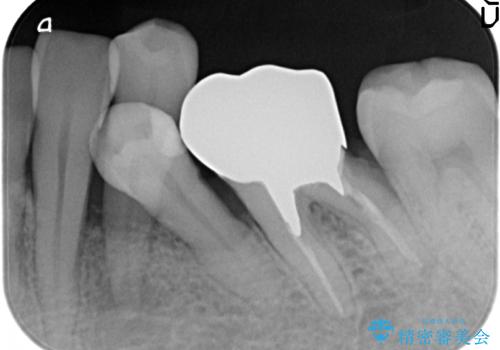

- 左下の歯並びが悪く、左側で物が咬みにくいので診て欲しいといらっしゃった方の症例です。

歯列矯正は御希望されなかったため左下4、5番目の歯を抜歯し、インプラントによる欠損補綴を行いました。

左下6も再根管治療後、オールセラミッククラウンによる補綴を行いました。